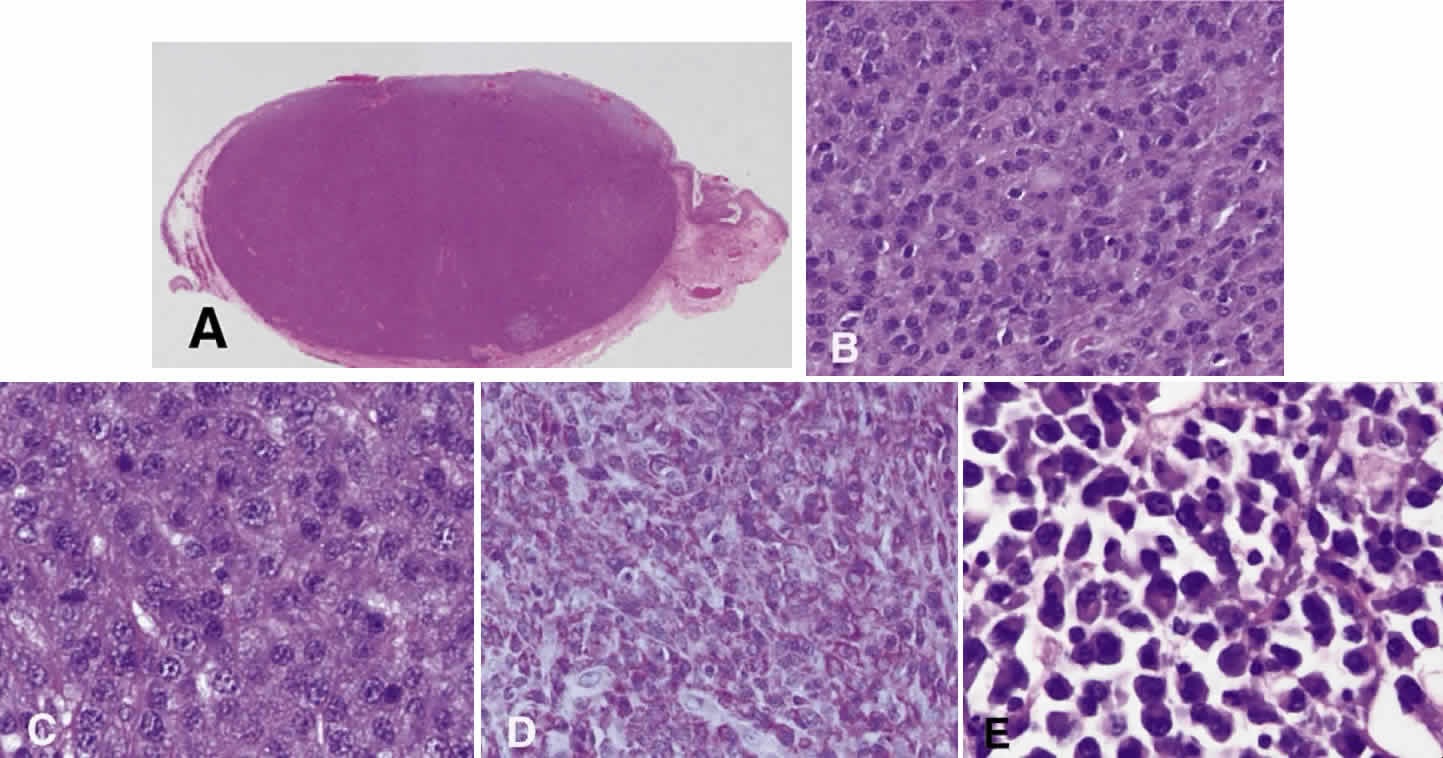

Numerous attempts have been made to classify lymphoid processes for clinical management and prediction of prognosis. Early classifications included only disease localized to the lymph node, which made classification of extranodal disease difficult and inaccurate. The Rappaport classification, first developed in 1956 and then modified in 1978, attempted to categorize lymphomas in two ways, first, using cytologic characteristics identified by conventional stains, and second, distinguishing between the follicular and diffuse growth pattern histologically38,39 (Table 3). The distinction of nodular, or follicular, and diffuse growth was considered useful because of the generally indolent nature of follicular growth, in which the tumor cell aggregates resemble germinal centers and disrupt the normal architecture of the node, compared with the appearance of diffuse growth, in which the lymph node is completely obliterated by a dense monotonous sheet of lymphocytes. In subsequent years, however, it was found that the descriptive growth pattern and cytogenetic characteristics of the Rappaport system did not predict prognosis reliably and were biologically inaccurate. The complexity of correlating degrees of differentiation, mitotic activity, and cytologic characteristics to prognosis have made lymphomas difficult to classify and have led to subsequent systems. The second system, proposed by Lukes-Collins in 1974, classifies lymphoma histologically according to its normal counterpart B-cell, T-cell, or null cell origin40,41 (see Table 3). Histologically, cells may appear small cleaved, large cleaved, small noncleaved, or large noncleaved, depending on the stage of B-cell arrest during normal transformation to immunoblast. Ninety percent of lymphomas are of B-cell origin, and the null cell also usually is of B-cell origin, although 10% may originate from T cells or histiocytes.42,43 Burkitt's lymphoma, the only lymphoma common in children, is a B-cell variant with a background of reactive histiocytes. As a result of histologic classification by Lukes-Collins, 76% of histiocytic lymphomas according to the Rappaport system were found to be not of histiocytic origin but of lymphocytic origin.40,44 The third system, the Working Formulation devised by the National Cancer Institute in 1982, attempted to predict prognosis by grouping lymphoma according to natural history, response to therapy, and overall survival.45 Three broad categories were established in terms of 5-year survival rates, the low-grade with a 50% to 70% survival rate, intermediate with 35% to 45%, and high grade with 23% to 32% (see Table 3). Orbital reactive hyperplasia, a relatively low-grade lesion, can be associated with systemic disease, whereas malignant or high-grade orbital lymphomas may be isolated findings. The Ann Arbor Staging Classification for Hodgkin's and non-Hodgkin's lymphomas was developed to stage disease based on systemic areas of involvement as a means of establishing a baseline for treating disease and following clinical progression46 (Table 4). Histologic classification, however, has been recognized as more useful than localization in the clinical management of nonHodgkin's lymphoma.47

While the Lukes-Collins and Working Formulation classifications were in wide use in the United States, the European literature made references to the Kiel and updated Kiel classifications, which led to disparities in classifying lymphoma. Another classification proposed by Jakobiec and coworkers was the most comprehensive classification available for orbital disease but failed to integrate systemic lymphoma, which is known to be associated in approximately half of cases.1 The most recent classification has made the system universal, comprehensive, and useful to interdisciplinary teams that characteristically manage patients with lymphoma. The International Lymphoma Study Group in 1994 developed the Revised European-American Lymphoma (REAL) classification (Table 5), which classifies lymphoid disease by the cell of origin into B-cell, T-cell, and natural killer cell lymphomas, leukemias, myeloma, and variants of Hodgkin's disease26 (Fig. 4). The identification of the putative benign progenitor cells has been inferred through the use of cell marker studies. The results of molecular genetic studies to identify immunoglobulin gene rearrangements and cytogenetic studies to detect chromosomal translocations in monoclonal proliferations have also been incorporated. A significant contribution of the REAL classification has been to incorporate primary extranodal lymphomas as recognizable and classifiable entities. As a result, new variants in this list include lymphoplasmacytic lymphoma, mantle cell lymphoma, marginal zone B-cell lymphoma, particularly mucosal-associated lymphoid tissue (MALT) lymphoma, subclasses of large cell lymphoma, and the natural killer cell lymphomas. Comparisons of the REAL classification to the Working Formulation and the Kiel classification are shown in Tables 6 and 7, respectively.48 The first series of 112 orbital lymphomas using the REAL classification reported the accuracy and utility of the system in classifying orbital lesions and predicting prognosis in combination with currently available immunophenotyping and immunocytogenetic studies.49 The REAL classification does not classify disease based on the degree of differentiation or clinical prognosis. However, a proposed prognostic scheme has been developed in accordance with the REAL classification28 (Table 8). In this text, tumor nomenclature adheres as strictly as possible to the REAL classification.